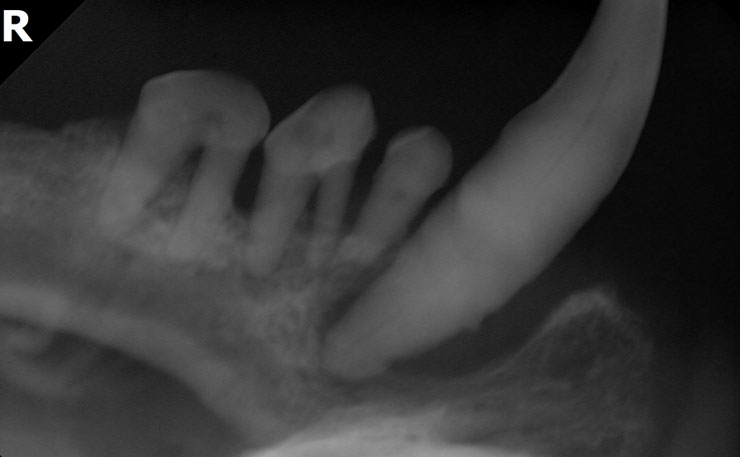

歯周病の歯科治療

たむら動物病院ではまず、歯科検診を行います。次に歯科処置が必要な場合、基本的にすべて全身麻酔下で行っております。そして歯科X線検査にて抜歯の必要性を検討し、必要があれば抜歯処置を行い、残った歯のスケーリング・ルートプレーニング・ポリッシングを行います。